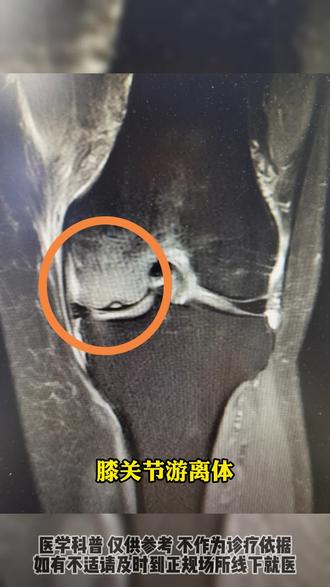

关节游离体又称为关节数,他是指关节内出现正常关节内没有的碎块。 关节游离体多见于膝关节和肘关节,特别是膝关节内游离体多见。膝关节内游离体可导致行走时膝关节突然出现卡顿、绞索, 严重时患者膝关节完全不能活动,出现摔倒,并伴有膝关节剧烈疼痛、肿胀、积液等症状。 导致膝关节内出现有立体的病因。主要有膝关节内软骨病变、骨缀、 膝关节滑膜病变、膝关节内骨折、痛风和膝关节半月板损伤等等。

就是针对刚才那个病人的病情呢,咱们正好谈一下,是膝关节游离体,膝关节游离体呢?呃,顾名思义,它是游离出去的一个小东西,那是什么东西呢?一般来说呢,你看这膝关节的模型,它都是这个膝关节腔里边呢, 呃,他损伤掉落的一些软骨片,像这种呢是最常见。这些软骨片呢,在这个膝关节里面游离出去以后呢,因为他还受到这个膝关节的这个滑液的这个营养,所以他这个软骨片可能会形成,慢慢的他会形成一个 呃,小瘤,就是小软骨瘤这么一个小东西,他在这个膝关节腔里边呢,转来转去不怕,最怕的是什么呢?怕的是他卡到咱们膝关节的关节缝里,就是突然间卡到这些髌骨关节缝或者十字韧带中间的一些关节缝里,他 他就会造成咱们膝关节突然间的不能取真活动和剧烈的疼痛。这种呢在咱们医学上呢,叫做膝关节的交锁的症状,这种症状一旦出现呢,对 病人呢,对这些患病的朋友,他的生活质量影响是非常大的。你想想,如果一个老人,他在过马路的时候,或者上下车的时候,突然间突然间出现膝关节的交锁,是多么可怕的一件事。所以像膝关节游离体一旦 出现膝关节交阻的症状,还是建议尽快的到医院去就诊,做一些相应的检查。如果确定是膝关节有理体这个病, 我们骨科大夫还是建议尽快的做一个呃膝关节颈的这种常规的颈下的微创手术,把它取出来。因为针对膝关节又离体这种病来说呢,如果你光靠吃药 打针呢?是没有办法把这个游离体给它消除掉的,所以说只能靠咱们进一个小镜子把它拿出来才能彻底的根治。